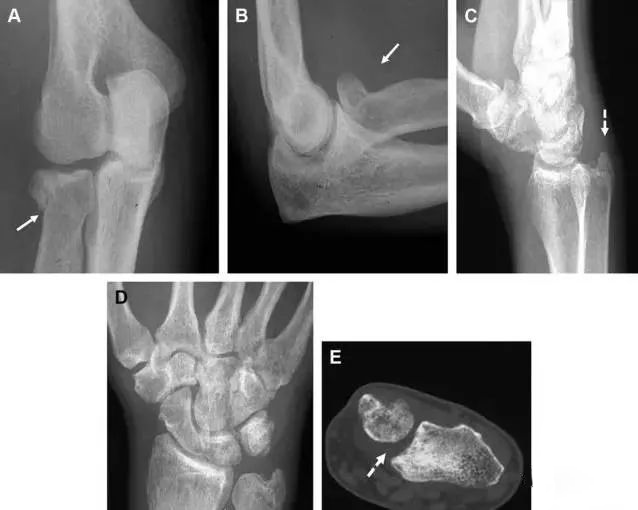

(1)Essex-Lopresti 骨折

是桡骨头骨折伴有下尺桡关节脱位,导致骨间膜损伤,桡骨短缩。此种损伤,桡骨头骨折的诊断往往是明确的,容易忽视的是下尺桡关节脱位,特别是早期,下尺桡关节的症状不明显,X 线表示也不明显。

前后位(A)和侧位(B)示桡骨头关节内骨折(白色实线箭头);(C~E)伤后 1 个月复诊,患者诉腕关节疼痛,X 线(C,D)发现下尺桡关节脱位,(E)CT 进一步证实损伤的存在。